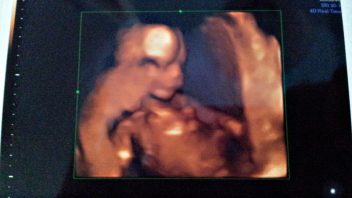

Zuzana se v 18. týdnu těhotenství. Co se děje s jejím tělem?